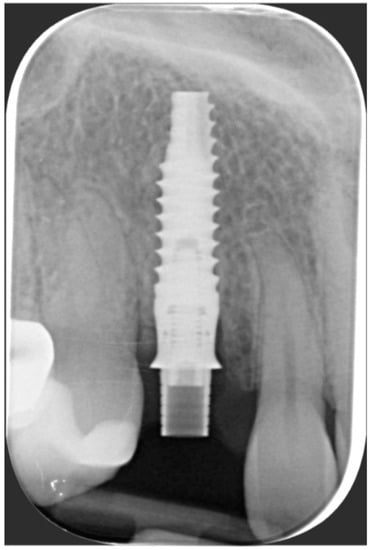

Figure 2. Radiographic evaluation revealing internal root resorption.